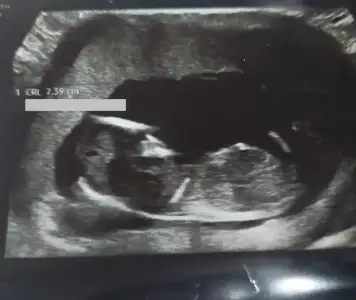

Banada tahminde bulunabilir misiniz? Kendi doktorum erkeğe benziyor başka bir doktor kıza benzettiği söyledi